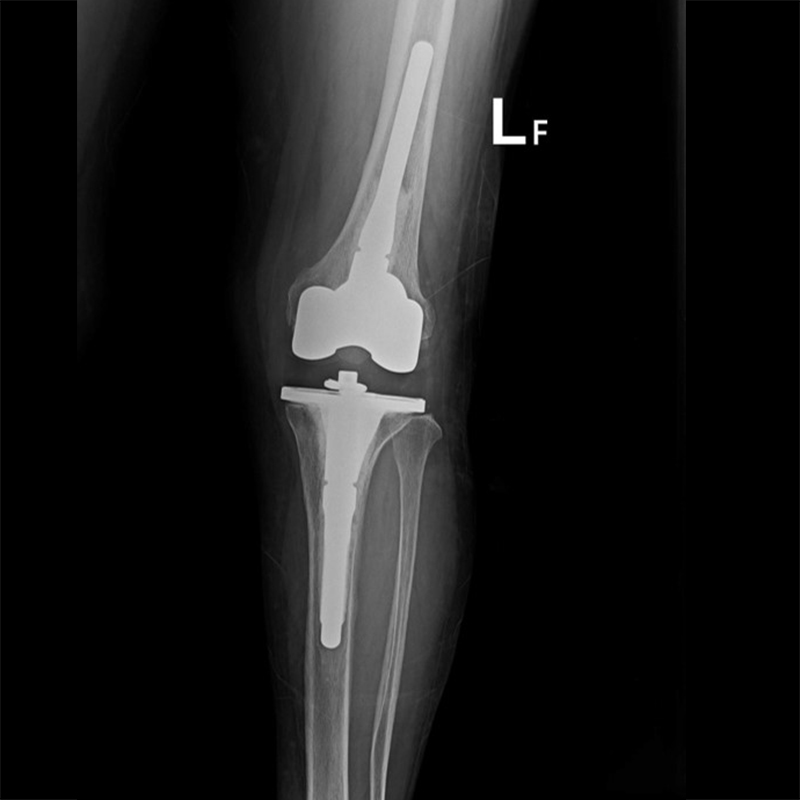

外院失敗本院再置換 首頁 案例分享 膝關節手術 外院失敗本院再置換 蕭女士 69歲 術前 術後 81歲 林女士 術前 術後 蕭女士 69歲 術前 術後 鄒女士 69歲 術前 術後 李女士 74歲 術前 術後 吳女士 71歲 術前 術後 謝女士 65歲 術前 術後